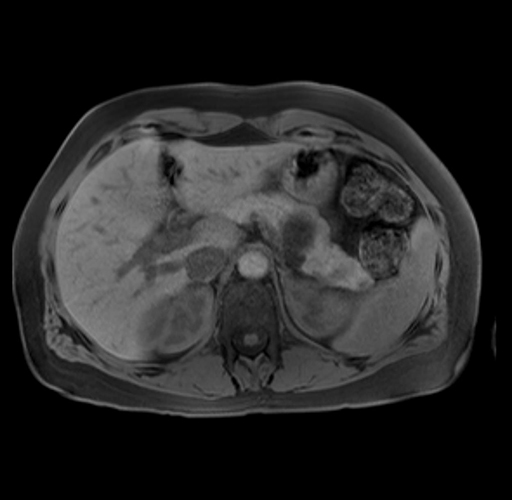

Imaging Analysis

Look through the patient's CT scan to identify any areas of concern for the necessary procedure.

Based on your CT findings, which issue(s) are present and would give reason for "planned slowing down moment(s)" in this case?